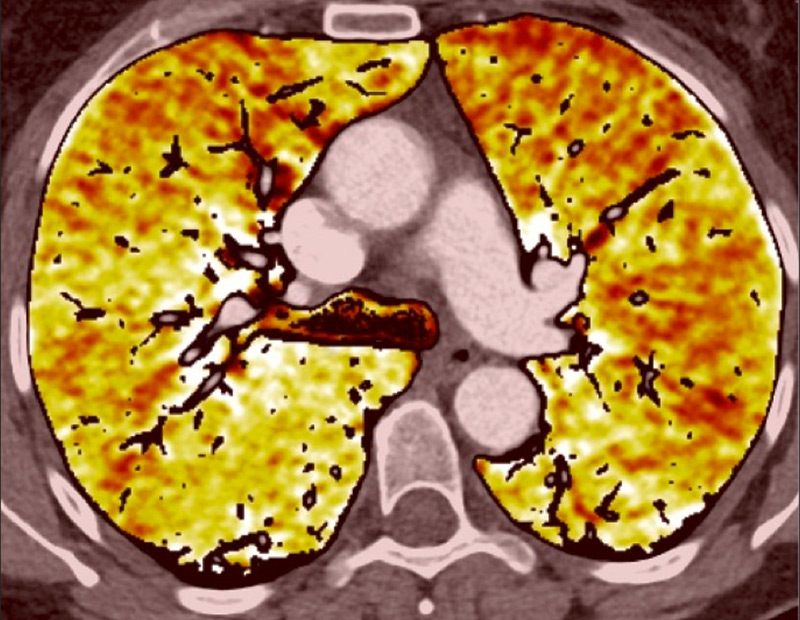

Because of the attenuation properties of iodine at two different photon energies (80 and 140 kV), a dual-energy technique can generate pulmonary blood volume maps and quantify the iodine concentration in the parenchyma. It has been demonstrated that the local distribution of iodine contrast medium correlates well with pulmonary perfusion [18]. The generated pulmonary blood volume maps are combined with mediastinal images to permit simultaneous analysis of the grey-scale vasculature and colour-scale parenchymal perfusion, with parenchymal images (fig. 1). Furthermore, the iodine concentration in the lung allows an objective and quantitative analysis.

Figure 1

Technical principles. The dual-energy system with two X-ray tubes permits simultaneous 80 (A) and 140 kV (B) image acquisition in order to generate an iodine map (C) fused with mediastinal reconstructions (D).